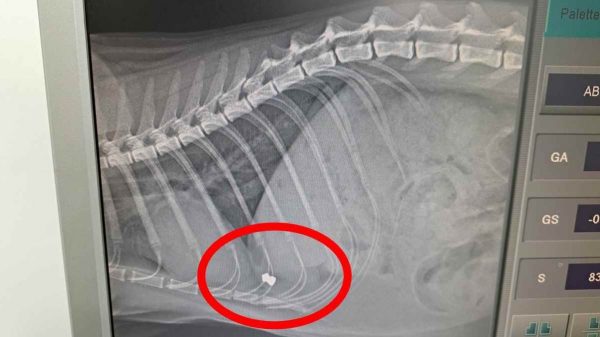

Ο γάτος στάθηκε τυχερός μέσα στην ατυχία του - Οι ιδιοκτήτες δηλώνουν αποφασισμένοι να βρουν τον υπεύθυνο ξεκαθαρίζοντας ότι δεν θα αφήσουν τη βαρβαρότητα να περάσει ατιμώρητη